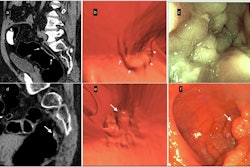

Editor's note: the image used to introduce this article on the homepage is a CTC of a 9-mm polyp (arrow) in the descending colon of a 78-year-old woman. Virtual fly-through 3D reconstructions were used for exact polyp localization. Courtesy of Dr. Sergio Grosu and colleagues from Ludwig Maximilian University of Munich and the RSNA.